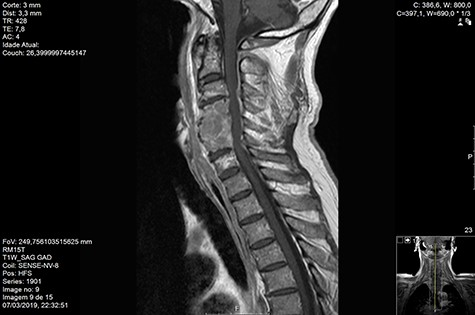

Computed tomography (CT) (Figs 1–3) and magnetic resonance imaging (MRI) (Figs 4–6) of the cervical spine were performed and revealed a lytic lesion involving most of C4, C5 and C6 vertebral bodies with bilateral extension to the posterior spinal elements of C4 and C5 and complete disruption of C4-C5 and C5-C6 intervertebral discs.

The Spinal Instability Neoplastic Score (SINS) [4, 6, 7] for assessing spinal instability from metastatic disease was used and the lesion was deemed unstable (SINS 13), with impending risk of increased neurological damage.

MRI and CT scans performed at 90 days post-radiation therapy showed an arrest of further progression of instability and resolution of the lytic lesion (Figs 7–13).